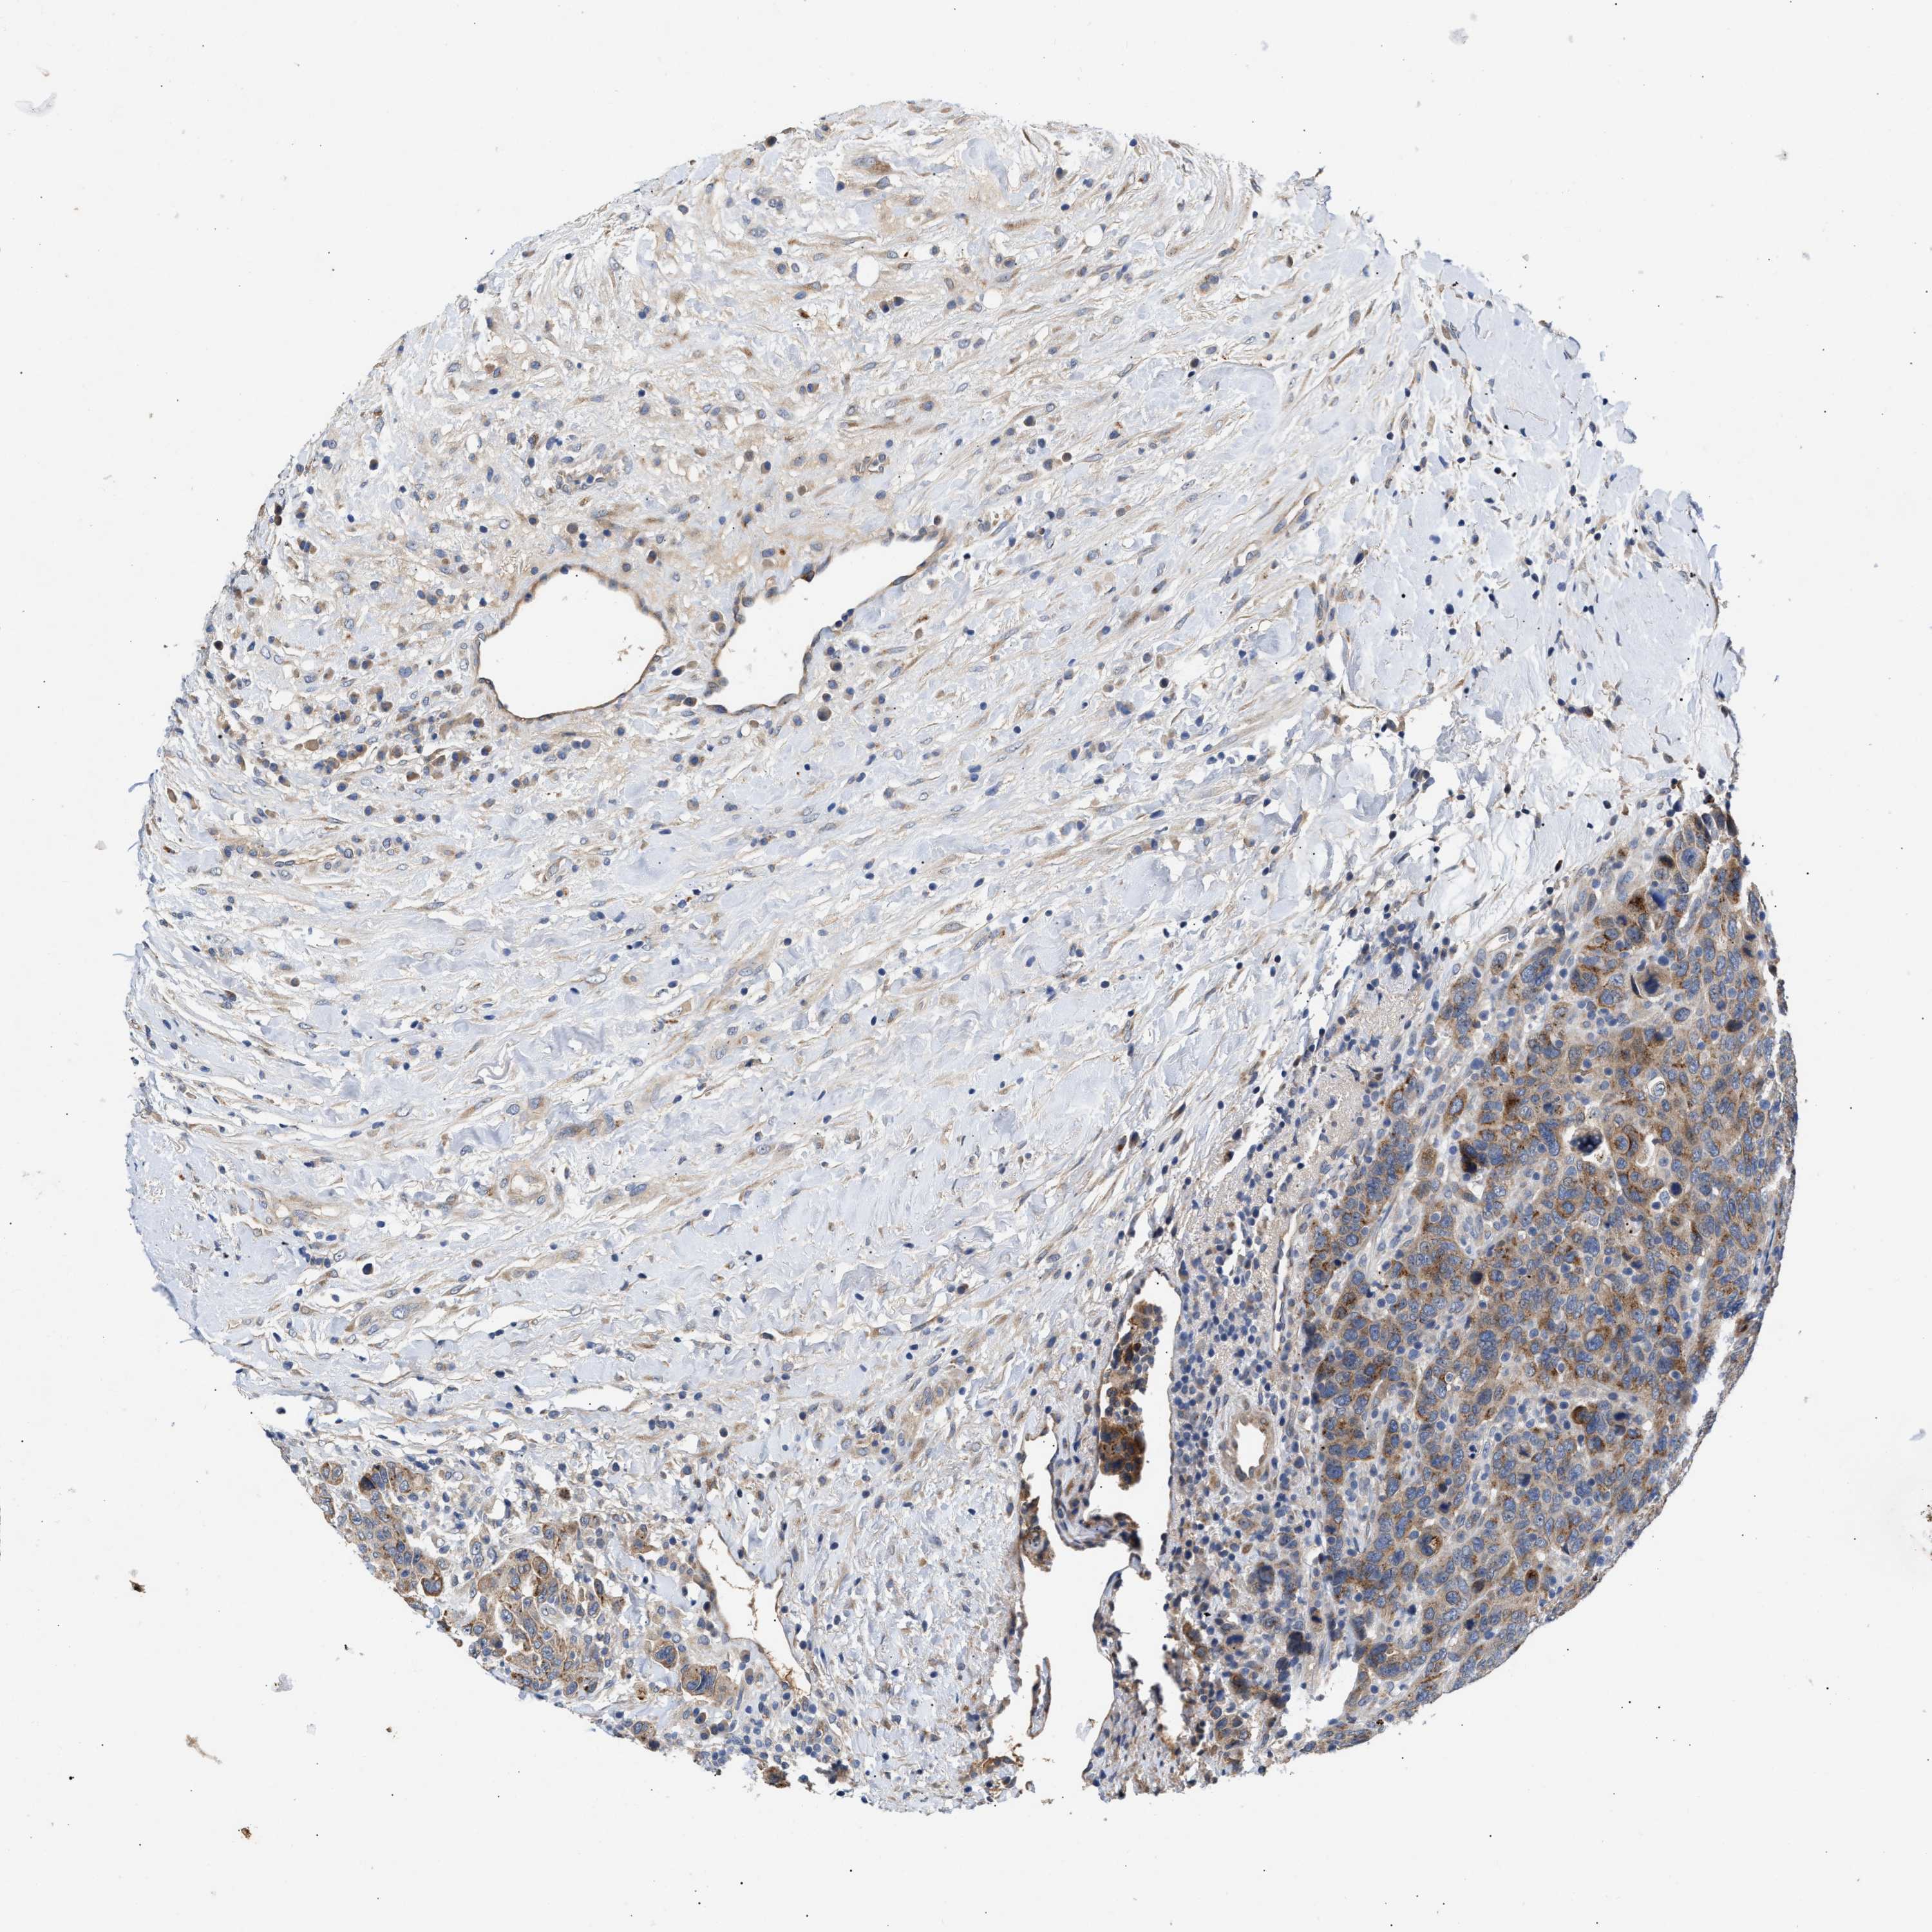

CANCER BREAST CANCER Show tissue menu

BRCA TCGA BRCA VALIDATION PROTEIN EXPRESSION

ANTIBODIES

AND

VALIDATION